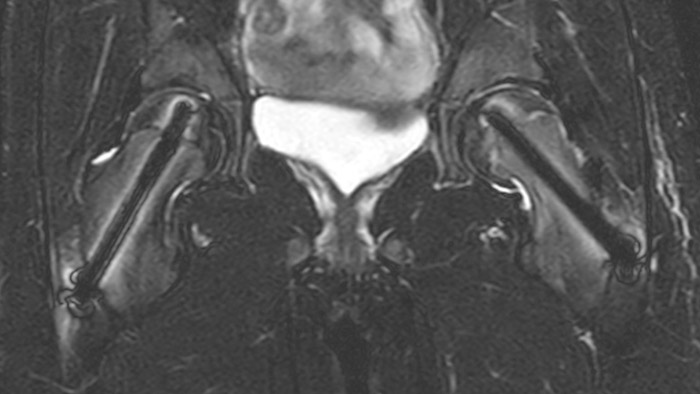

After intervention with two cannulated titan screws, it is important to check that the circumference is normal and without necrosis. The screws can cause major metal artifacts, but O-MAR allows to improve visualization of tissue and bone in the near vicinity of MR Conditional orthopedic implants1. 1 Only for use with MR Safe or MR Conditional implants by strictly following the Instructions for Use

Perthes disease in left hip The affected area on the upper circumference of the left hip shows contrast uptake in the dynamic scan. The radial scan nicely depicts the hip area, despite the dark shape in the center that is inherent to the radial way of scanning.